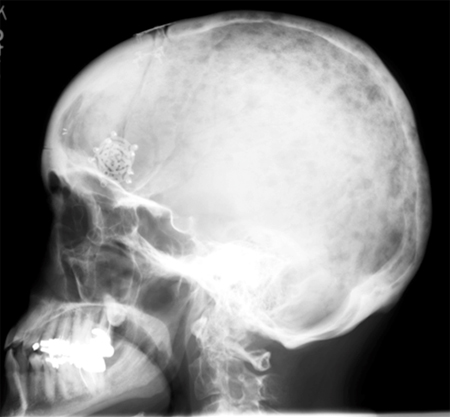

Avaliação de gamopatias monoclonais

Doença óssea no mieloma

Do acervo pessoal do Dr. Kumar